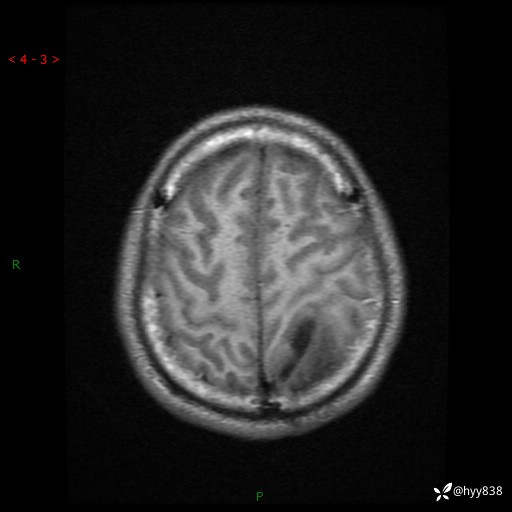

病例年轻小伙,头痛伴呕吐半年,渐进性加重1月。疑难病例,第一次见--结果公布~

性别:男

年龄:21岁

简要病史:头痛伴呕吐半年,渐进性加重1月

颅脑MRI平扫+增强